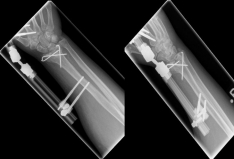

Pictures: In this case, the articular surface of the wrist was completely destroyed, so that only a therapy by means of outer retainer and some K-wires to correct the position was possible. Here is a practice only after removal of the outer holder after 6-8 weeks possible. Such severe joint injuries often lead to premature joint wear